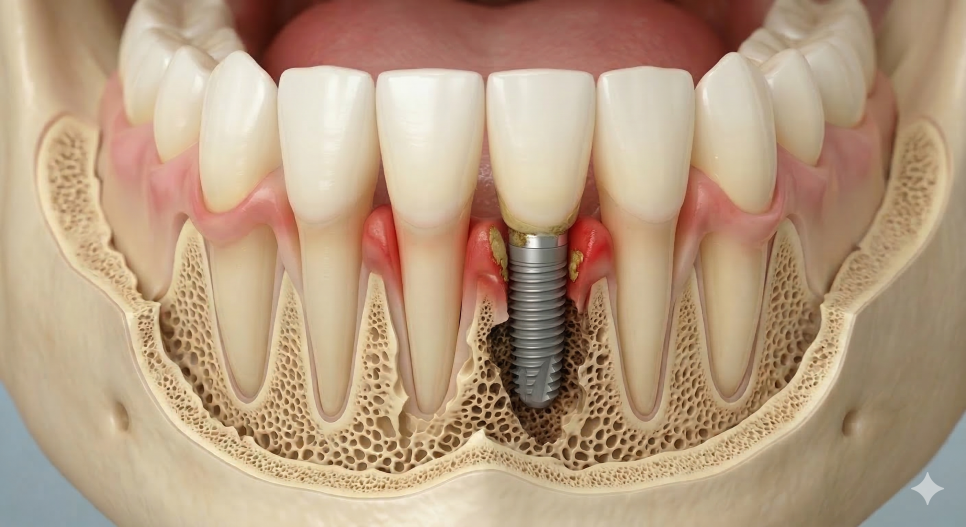

임플란트의 가장 큰 적,

임플란트 주위염이란?

임플란트는 인공 치아이기 때문에

자연치아와 달리 충치가 생길 걱정은 전혀 없어요.

하지만 그렇다고 해서

관리를 소홀히 해도 된다는 뜻은 아닙니다.

임플란트를 단단하게 지탱해 주는

주변 잇몸과 잇몸뼈에는

얼마든지 염증이 생길 수 있는데,

이를 임플란트 주위염이라고 부릅니다.

보통 치아 사이에 남은 음식물 찌꺼기가

제때 제거되지 않아 딱딱한 치석이 되고,

그 안의 세균들이 독소를 내뿜으며

잇몸뼈를 서서히 녹이게 되는 것이 주된 원인이에요.